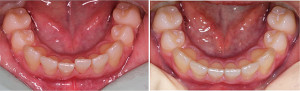

Primer indikacije in ortodontsko zdravljenje s termoplastično opornico v spodnjem zobnem loku. Čas zdravljenja 1 mesec. Terapevt: Karmen Verhovec, dr. dent. med., spec. ortodont, ZoboEstetika d.o.o. | Zobotehnični laboratorij: Tanilab dentalni laboratorij d.o.o.